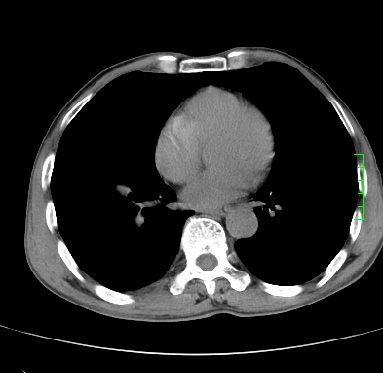

m,73y。膝关节疼痛伴双下肢水肿。入院常规胸片发现结节灶。增强为静脉期。

浅分叶、棘突,考虑右下肺周围型肺癌

考虑周围型肺癌  ,双上肺结核。

肿块周围可见局限性气肿,考虑肺癌可能性大。双肺上叶继发型肺结核。

指套征,强化明显,近侧肺组织局限性肺气肿,考虑支气管类癌,慢支、肺气肿、双上陈旧性tb、冠脉钙化。

鉴别:先天性支气管闭锁,变态反应性支气管肺曲霉菌病,肺癌,支气管囊肿,支扩黏液嵌塞。

1)考虑右肺下叶周围型肺癌。2)右肺上叶及左肺感染性病变(结核可能)。3)肺气肿。4)冠状动脉钙化。